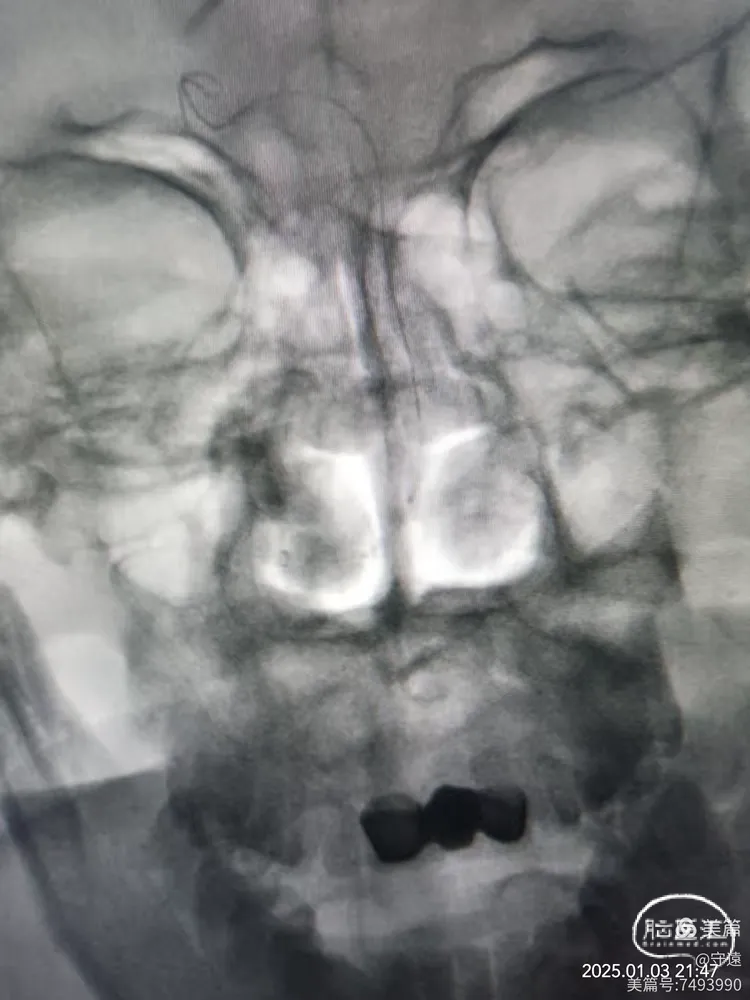

核磁显示:双侧桥臂,右侧丘脑梗塞。

MRA示:双椎动脉、基底动脉中下段未显影。

双侧椎动脉及基底动脉中下段末显影影,左侧后交通向基底供血。